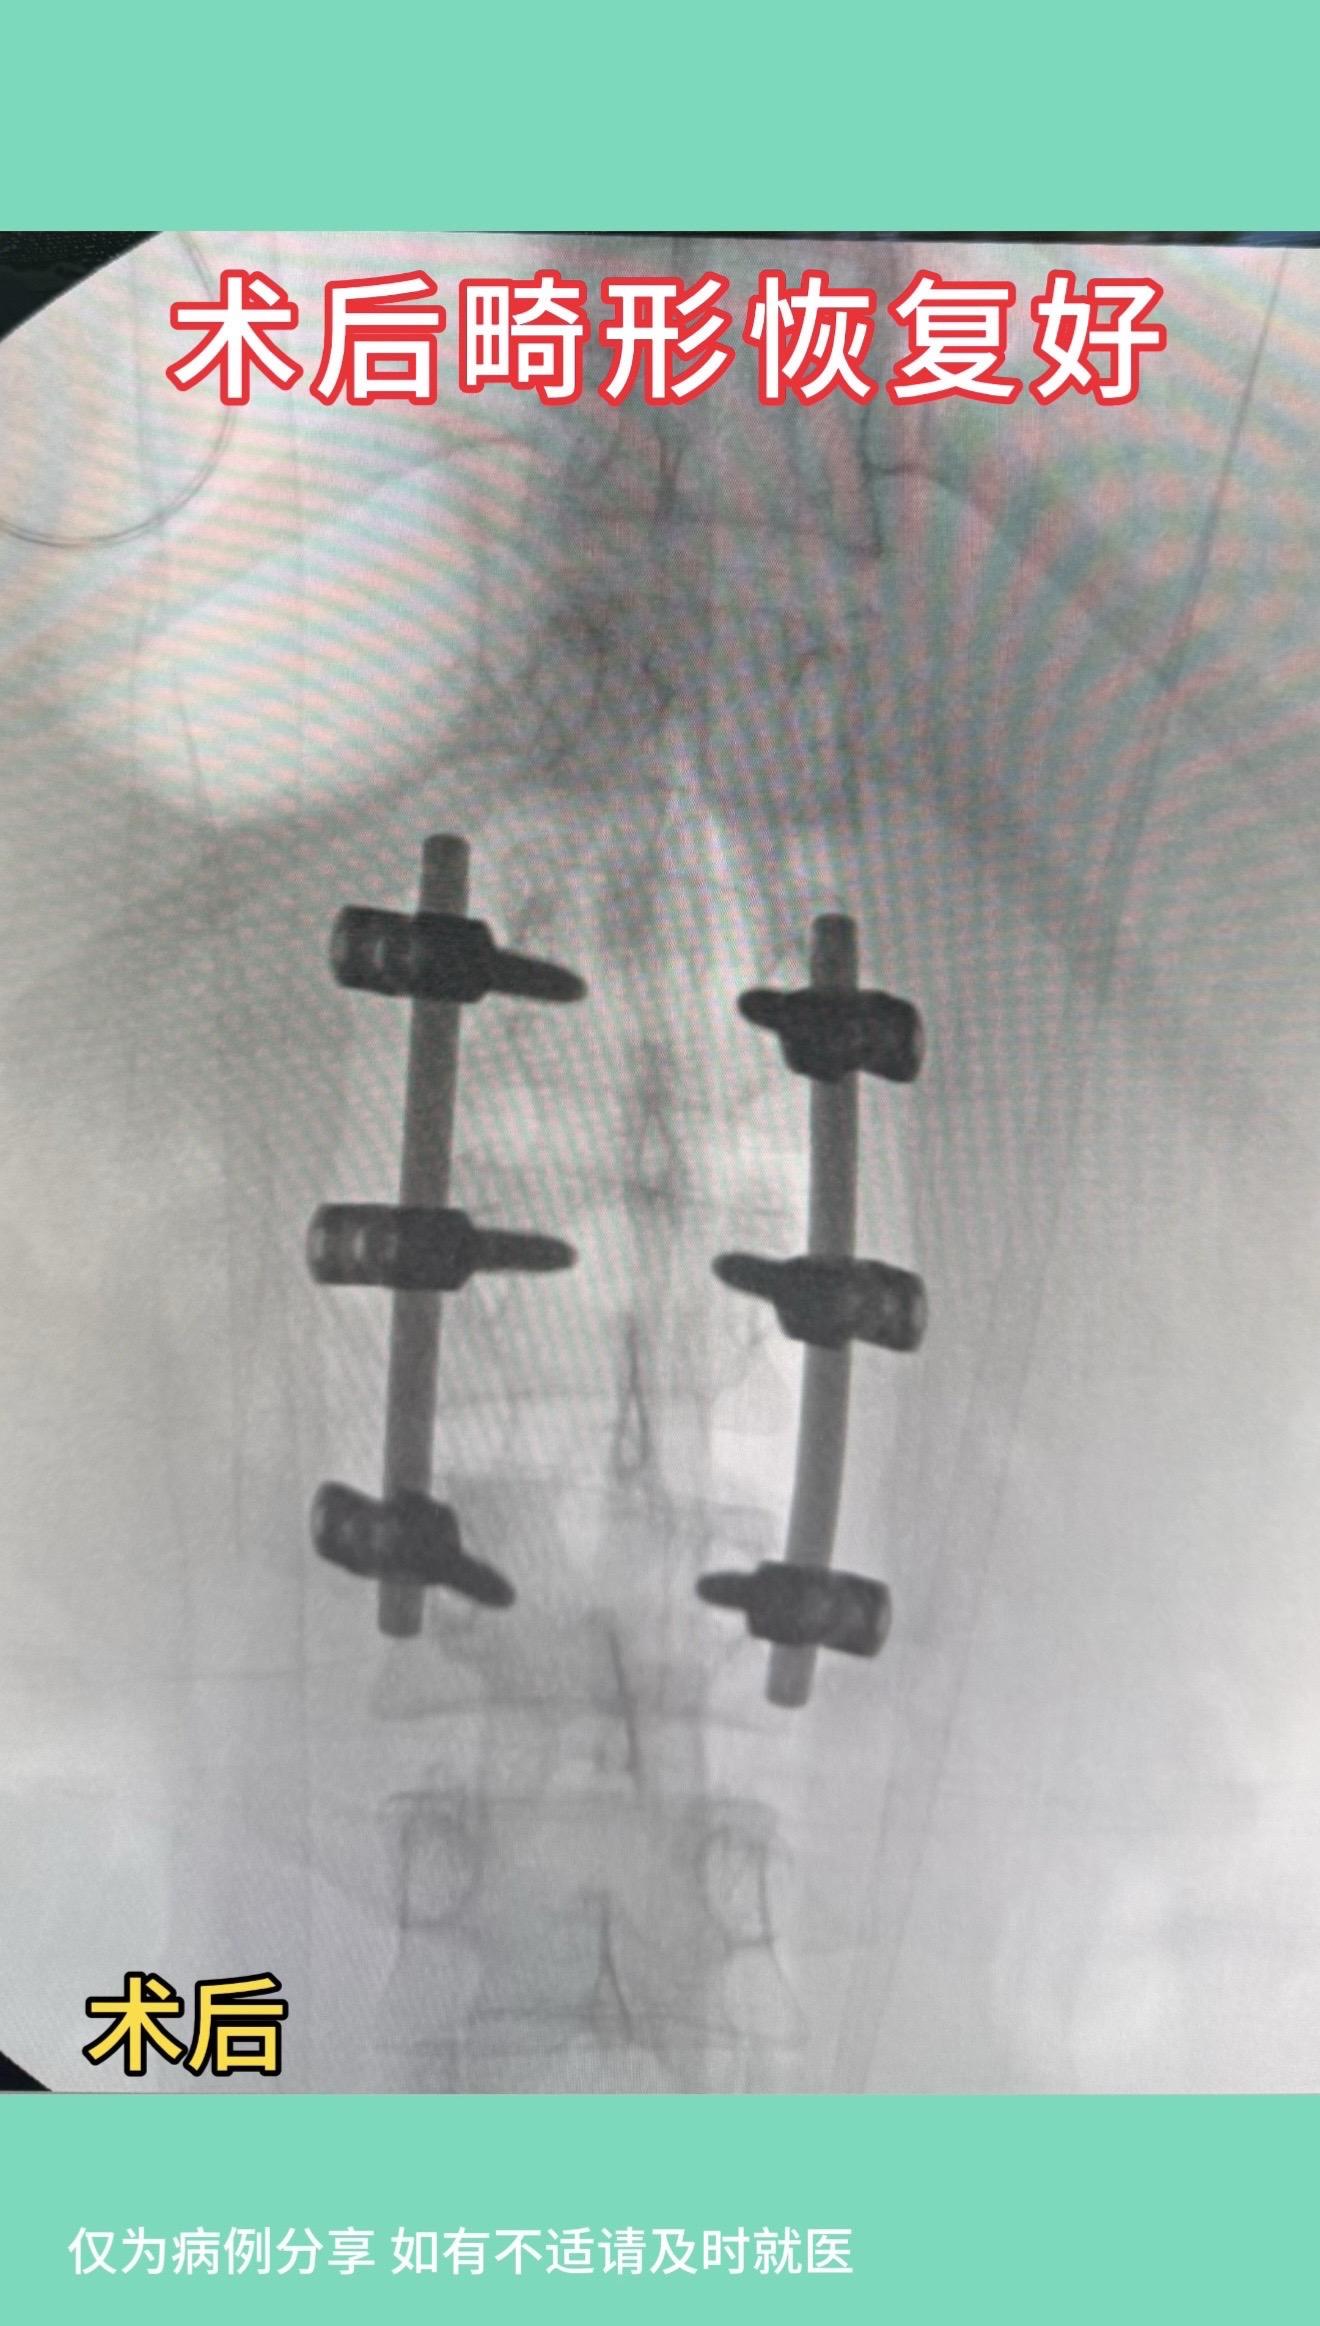

17岁女孩,车祸后腰1骨折伴侧弯,旋转畸形。术后畸形恢复好。